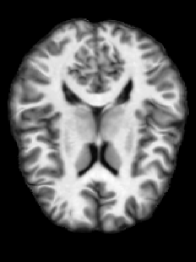

In a first step, we consider a pair of representative images of the OASIS-1 dataset. We show the registration results in Figure 3. We illustrate the computed spatial transformation in Figure 4. We report the DICE scores for the four ROIs in Table 1. We report additional performance measures in Table 2. We report measures for the difference of the composition of the forward map and its inverse from identity in Table 3.

Based on the results for registration accuracy reported in Table 1 and Table 2, we observe that all methods yield competitive results. This is qualitatively confirmed by the visualizations shown in Figure 3. Overall, VPreg yields a slightly better DICE score for the four anatomical regions considered in this study. Easyreg yields the best MSE-ratio and MI-incr. Overall, we conclude that our method is competitive in terms of registration accuracy for this exemplary pair of images.

If we turn to properties of the deformation map, we can observe that VPreg yields well-behaved maps. In particular, VPreg yields diffeomorphic transformations and at the same time provides an accurate approximation of their inverse. This can be seen qualitatively in Figure 4 and, more importantly, is quantified in Table 2 and Table 3. The maps generated by ANTs and Easyreg are not diffeomorphic as judged by the minimal value of the determinant of the Jacobian of the transformation in Table 2. Those generated by Fnirt are. We emphasize that the numerical guarantees on generating diffeomorphic maps VPreg provides do not negatively affect registration accuracy as confirmed by the DICE scores reported in Table 1. These observations are also confirmed by the visualizations shown in fig. 4.